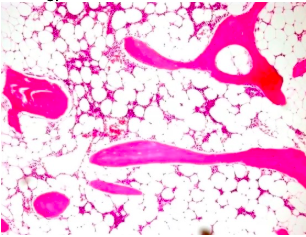

Describe the histological appearance of cancellous bone.

Trabeculae are dark pink areas and in between you will find adipose tissue with haemopoietic cells